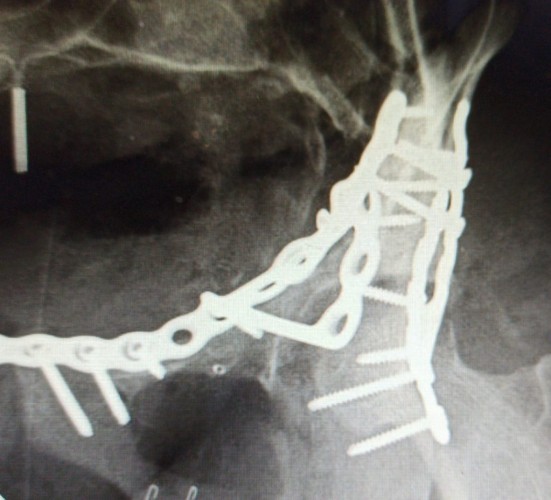

واصلت مدينة الملك سعود الطبية ممثلة بجراحات العظام وكسور الحوض، نجاحاتها في العمليات النادرة والمعقدة، حيث أنقذت أربعينية من إعاقة بالحركة جراء حادث مروري؛ نتيجة إصابتها  بخلع في فخذها الأيسر مع كسور مضاعفة في الحوض.

وأوضحت المدينة على لسان استشاري جراحة العظام وكسور الحوض والمشرف على الحالة د.حسين اليوسف، أن الحالة المعقدة كانت قد حولت لمدينة الملك سعود الطبية، بعد أن أجريت لها عملية جراحية قبل فترة لإرجاع كسور الورك، إلا أنها لم تتكلل بالنجاح.

وأشار د.اليوسف إلى أن الصعوبات في هذا النوع من العمليات تكمن في عدة أمور تتمثل في أن منطقة الحوض محاطة بأهم وأكبر الأوعية الدموية والأعصاب التي قد تؤدي إصابتها بحياة المريض أو تشل من حركته، بالإضافة إلى خطورة الالتهابات تزداد في حالات المراجعة والتي تجرى فيها العملية بعد عمليات سابقة في نفس المنطقة، كما أن الدراسات أثبتت تضائل نسبة النجاح في حال تأخر العملية أو إعادتها خصوصا عندما تكون الإصابة شديدة و نسبة التفتت عالية كذلك فإن التليفات الناجمة عن جروح عمليات الولادة تجعل الوصول إلى الكسر أمرا ليس بالسهل.

ونوه د.اليوسف بأن أنه بعد استقبال الحالة، تم إجراء تدخل جراحي على مرحلتين، حيث كانت الأولى عبارة عن إزالة الشرائح والتفتتات  من المفصل في الخلف ليقوم بعدها بإرجاع الكسر وترميم المفصل وتثبيته ليعود بعدها في المرحلة الثانية لتكرار العملية للجزء الأمامي من الكسر.

وأفاد د.اليوسف بأن العملية تكللت بالنجاح وحالة المريضة جيدة بعد إعادة الكسر وترميم المفصل ، وخضوعها للعلاج الطبيعي والتأهيل وهي الآن في طريقها للحركة الطبيعية بإذن الله.

تجدر الإشارة إلى أن عمليات جراحة الحوض والورك من العمليات المعقدة في جراحة العظام، وتُعد مدينة الملك سعود الطبية رائدة في هذا المجال بما تمتلكه من كفاءات مؤهلة ومتخصصة، وأصبحت مرجعاً هاماً يستقبل العدد الأكبر من هذه الإصابات من جميع أنحاء المملكة.